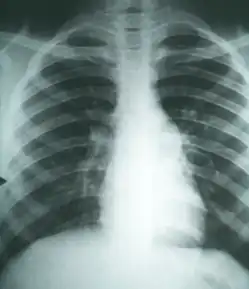

A case of pulmonary fibrosis caused by coccidioidomycosis

Coccidioidomycosis diagnosis relies on a combination of an infected person's signs and symptoms, findings on radiographic imaging, and laboratory results.[4] The disease is commonly misdiagnosed as bacterial community-acquired pneumonia.[4] The fungal infection can be demonstrated by microscopic detection of diagnostic cells in body fluids, exudates, sputum and biopsy tissue by methods of Papanicolaou or Grocott's methenamine silver staining. These stains can demonstrate spherules and surrounding inflammation.

Chest X-rays rarely demonstrate nodules or cavities in the lungs, but these images commonly demonstrate lung opacification, pleural effusions, or enlargement of lymph nodes associated with the lungs.[4] Computed tomography scans of the chest are more sensitive than chest X-rays to detect these changes.[4]